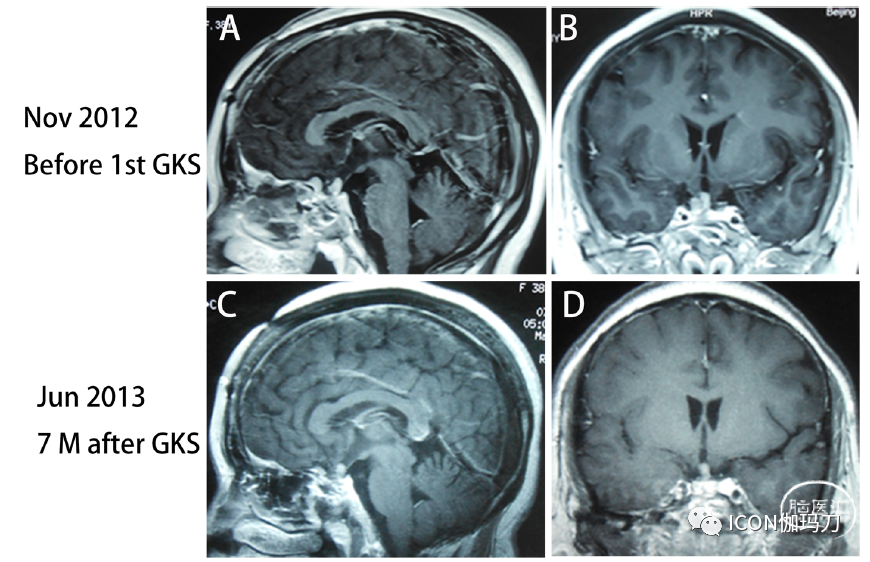

因为肿瘤继续生长或复发,2012年11月,她接受第一次伽玛刀放射外科治疗(GKS)治疗(图2A和B)。七个月星期治疗后,MRI显示肿瘤大小略下降(图2 C和D)和血清泌乳素水平降低了从200.0 ng / mL(样本不稀释)57 ng / mL。然而,2013年11月MRI显示肿瘤大小明显增大(图2E和F),血清泌乳素水平再次上升至289.0 ng/mL(补充图1),她接受了第二次GKS治疗。8个月后第二个星期的治疗,MRI在2014年7月表示,肿瘤大小略有缩小(图2 G和H)和血清泌乳素水平下降到126.0 ng / mL(补充图1)。尽管接受过两次GKS的治疗,再次在2014年10月她的症状视野缺损和右眼视力缺损。MRI显示肿瘤迅速扩大,鞍上延伸并包覆右侧ICA(图3A和B),血清泌乳素再次增加到339.0 ng/mL(补充图1)。视力减退症状明显改善,血清泌乳素水平降至108.0 ng/mL(补充图1)。肿瘤切除后病理检查显示有丝分裂活性增加,Ki-67指数上升至10%(图4B和C)。2014年11月推荐使用卡麦角林;然而,在卡麦角林治疗1个月后,肿瘤继续扩大,激素继续增加(补充图1)。然后,我们推荐替莫唑胺(TMZ)治疗,但她拒绝这种化疗,因为TMZ的费用过于昂贵,医疗保险无法覆盖垂体瘤患者使用该药的费用。

图2.(A)和(B)在第一次伽玛刀放射外科(GKS)治疗前,2012年11月MRI报告肿瘤位于鞍区和鞍上区。(C)和(D)第一次GKS治疗7个月后,MRI显示肿瘤大小略有缩小。(E)和(F)第二次GKS治疗前,2013年11月MRI显示肿瘤大小再次明显增大(Knosp分级4级)。(G)和(H)第二次GKS治疗8个月后,2014年7月MRI显示肿瘤大小略有减小。